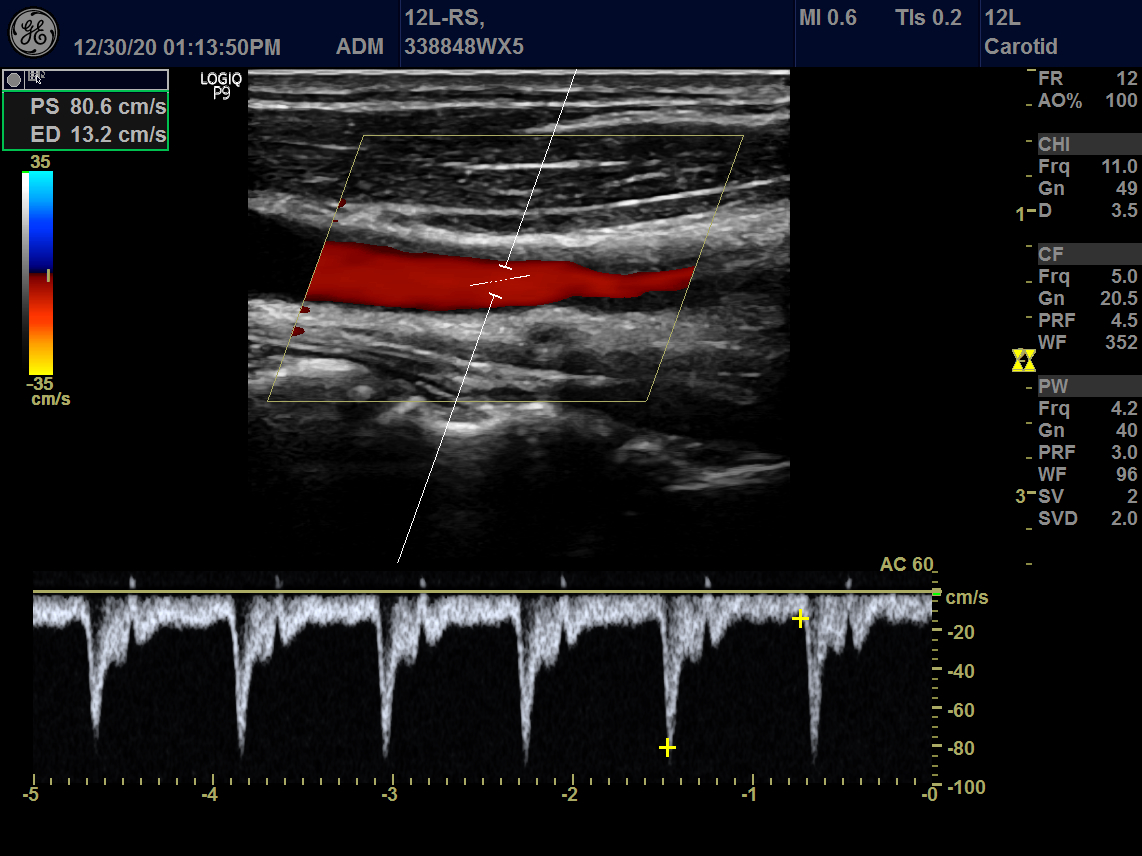

GE 12L-RS Vascular Linear Refurbished

GE Linear 12L-RS Vascular

Intended use

Vascular, Small Parts and Musculoskeletal

Frequency Range

13 – 4 MHz

GE 12L-RS Vascular Linear

Frequency Range: 13 – 4 MHz

GE 12L-RS Vascular Linear for Vascular, Small Parts and Musculoskeletal